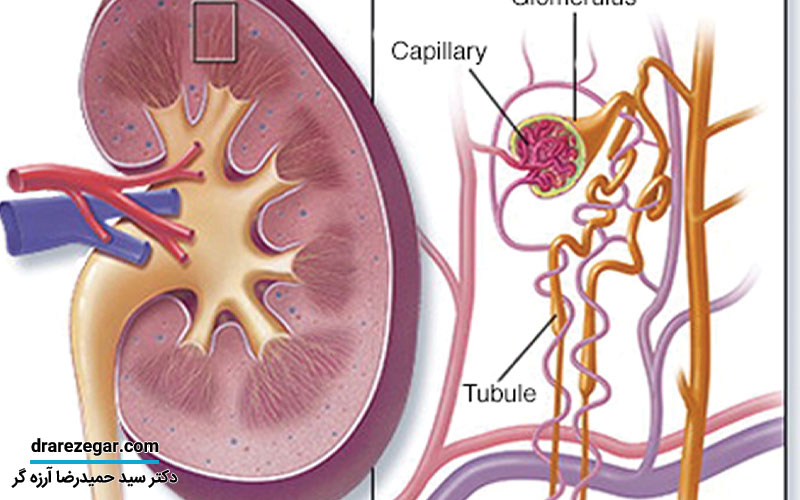

در خون هر فرد پروتئین وجود دارد و پروتئین اصلی که در خون یافت می شود آلبومین است. کلیه ها می توانند مایع و مواد زائد را از خود جدا کنند اما سایر مواد مغذی از جمله پروتئین را عبور داده و آن را در جریان خون بر می گردانند. زمانی که کلیه عملکرد درستی نداشته باشد، برخی از پروتئین ها را مثل آلبومین از فیلتر عبور می دهد و آن را وارد ادرار می کند. علائم دفع پروتئین در ادرار می تواند نشان دهنده یک بیماری جدی باشد که باید در سریع ترین زمان ممکن درمان شود. برخی اوقات این وضعیت نشان دهنده اختلالات و بیماری هایخاصی است اما در بسیاری از موارد نیز افراد سالم دچار آن می شوند. در حالت نرمال مقدار پروتئین دفع شده از طریق ادرار ۱۵۰ میلی گرم و آلبومین ۳۰ میلی گرم است ولی با افزایش این مقدار می توان نتیجه گرفت که کلیه ها عملکرد درستی ندارند. جهت آشنایی با علائم دفع پروتئین در ادرار در این مقاله از سایت دکتر سیدحمیدرضا آرزه گر همراه ما باشید.

دفع پروتئین از ادرار در اثر گلومرولونفریت

رگ های خونی کوچک در کلیه و گلومرول ها ملتهب می شوند که همین امر باعث ایجاد مشکل گلومرولونفریت خواهد شد. در طی این عارضه پروتئین زیادی توسط کلیه ها دفع می شود که با یک آزمایش ساده قابل تشخیص است.

• برای بررسی عملکرد کلیه ها آزمایش میزان فیلتراسیون گلومرولی انجام می شود.